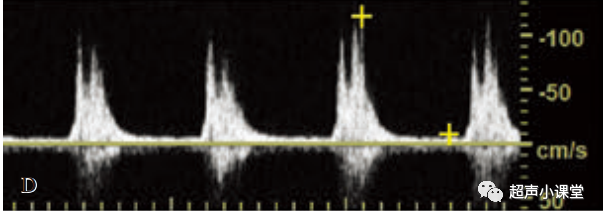

(三)狭窄近心段的搏动性改变

动脉阻塞后会导致狭窄近心段搏动性增强.典型例子如颈内动脉阻塞引起颈总动脉高搏动性,如下图

A图为患侧颈总动脉称高搏动性,表现为收缩峰陡直,大部分舒张期无血流.

B图为对侧正常颈总动脉频谱

需要注意的是,如此存在侧支循环,这样的高搏动性频谱表现的并不明显,频谱有时甚至趋于正常.